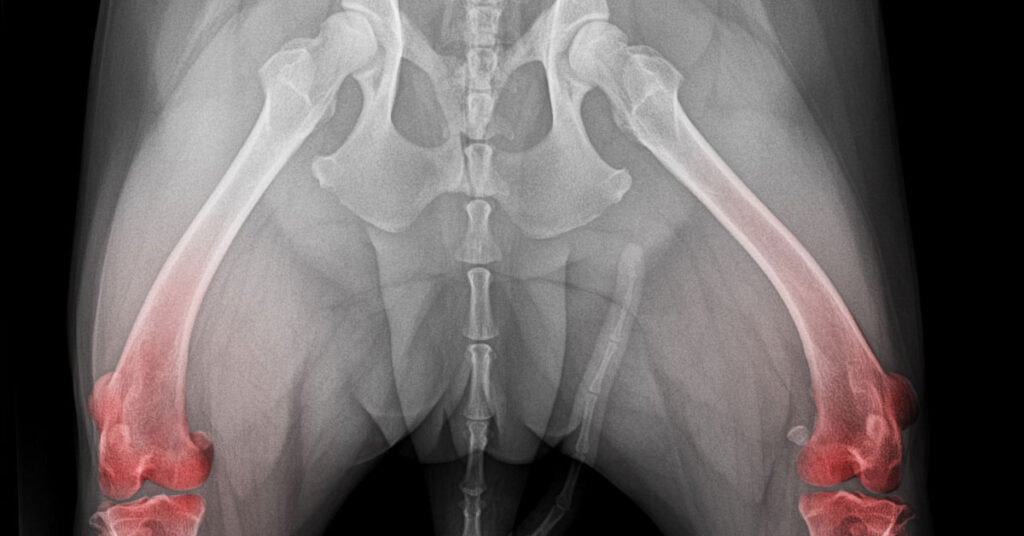

A dor associada com a displasia geralmente se intensifica à noite e pode aumentar com o tempo. Um sintoma notável em casos avançados é a deformidade conhecida como “fêmur em cajado de pastor”, uma curvatura característica do osso do quadril.

A avaliação inicial geralmente inclui um exame de raio-X, que pode revelar as deformidades típicas e outras características da displasia nos ossos.